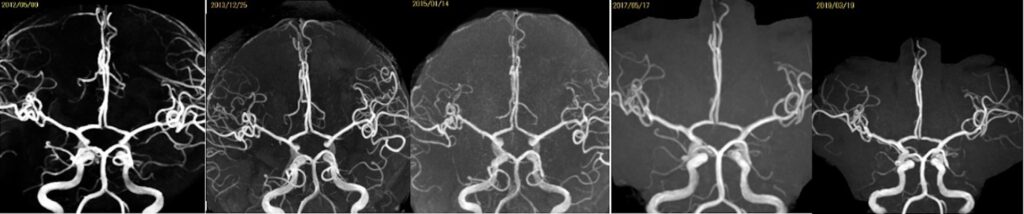

59歳女性の右中大脳動脈瘤を鍵穴クリッピングをしました。後遺症なしでした。 2025 12/12 脳動脈瘤・鍵穴 2025年12月12日13年前にくも膜下出血を起こしunknown SAHと診断され経過を見てきた患者さんに動脈瘤が徐々に育ってきたケースです。鍵穴クリップで対処しました。ScreenshotScreenshotScreenshotScreenshotScreenshotScreenshotScreenshotScreenshot 脳動脈瘤・鍵穴 よかったらシェアしてね! URLをコピーしました! URLをコピーしました! 251024金 橋本信夫先生に久しぶりにお会いしました。 251029水 第84回日本脳神経外科総会(パシフィコ横浜)初日 この記事を書いた人 kikuta 関連記事 未破裂中大脳動脈瘤の鍵穴クリッピング術を行いました。後遺症を認めませんでした。 2026年4月27日 2026年2月 52歳女性 左内頸動脈-眼動脈分岐部動脈瘤クリッピング術を行いました。 2026年3月21日 56歳女性 内頸動脈眼動脈分岐部動脈瘤クリッピング術をしました。軽度視野欠損が出ましたが無事退院されました。 2026年2月19日 63歳男性、右内頸動脈瘤開頭クリッピング術 2026年1月6日 58歳男性 中大脳動脈瘤を鍵穴クリップしました。合併症なく退院されました。 2025年12月17日 44歳女性 SAH PICA遠位部動脈瘤クリッピングを指導しました。 2025年12月17日 2025年5月 68歳女性未破裂Acom 動脈瘤6.6mmのクリッピング術 2025年9月26日 前交通動脈瘤をクリッピングしました 2025年2月26日